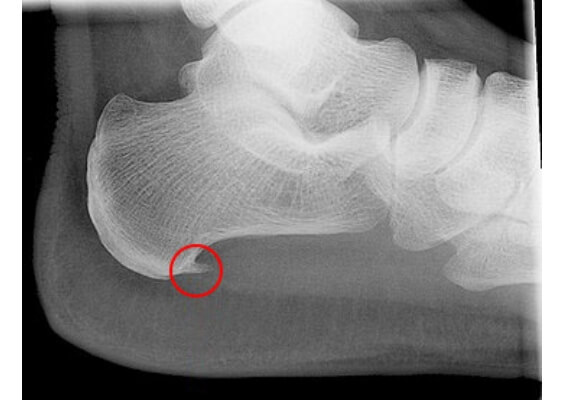

<画像所見>

レントゲンでは踵(かかと)にトゲ状(骨棘)の画像(※レントゲン画像参照)が認められることが多く、エコーでは微細損傷や炎症が認められることが多いです。

足底腱膜炎(足底筋膜炎)の画像所見